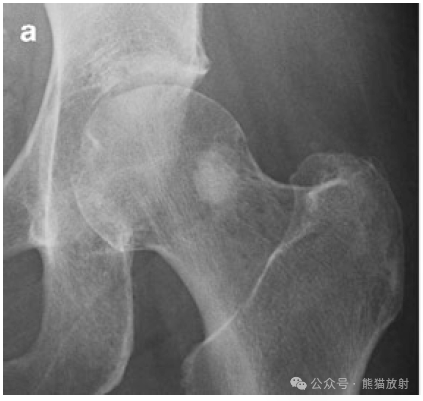

来源:熊猫放射 病史 56岁男性,左髋部疼痛。(A 56-year-old man with left hip pain.) 影像学表现 X线片(a)显示股骨颈见一圆形硬化性病变。Radiogra